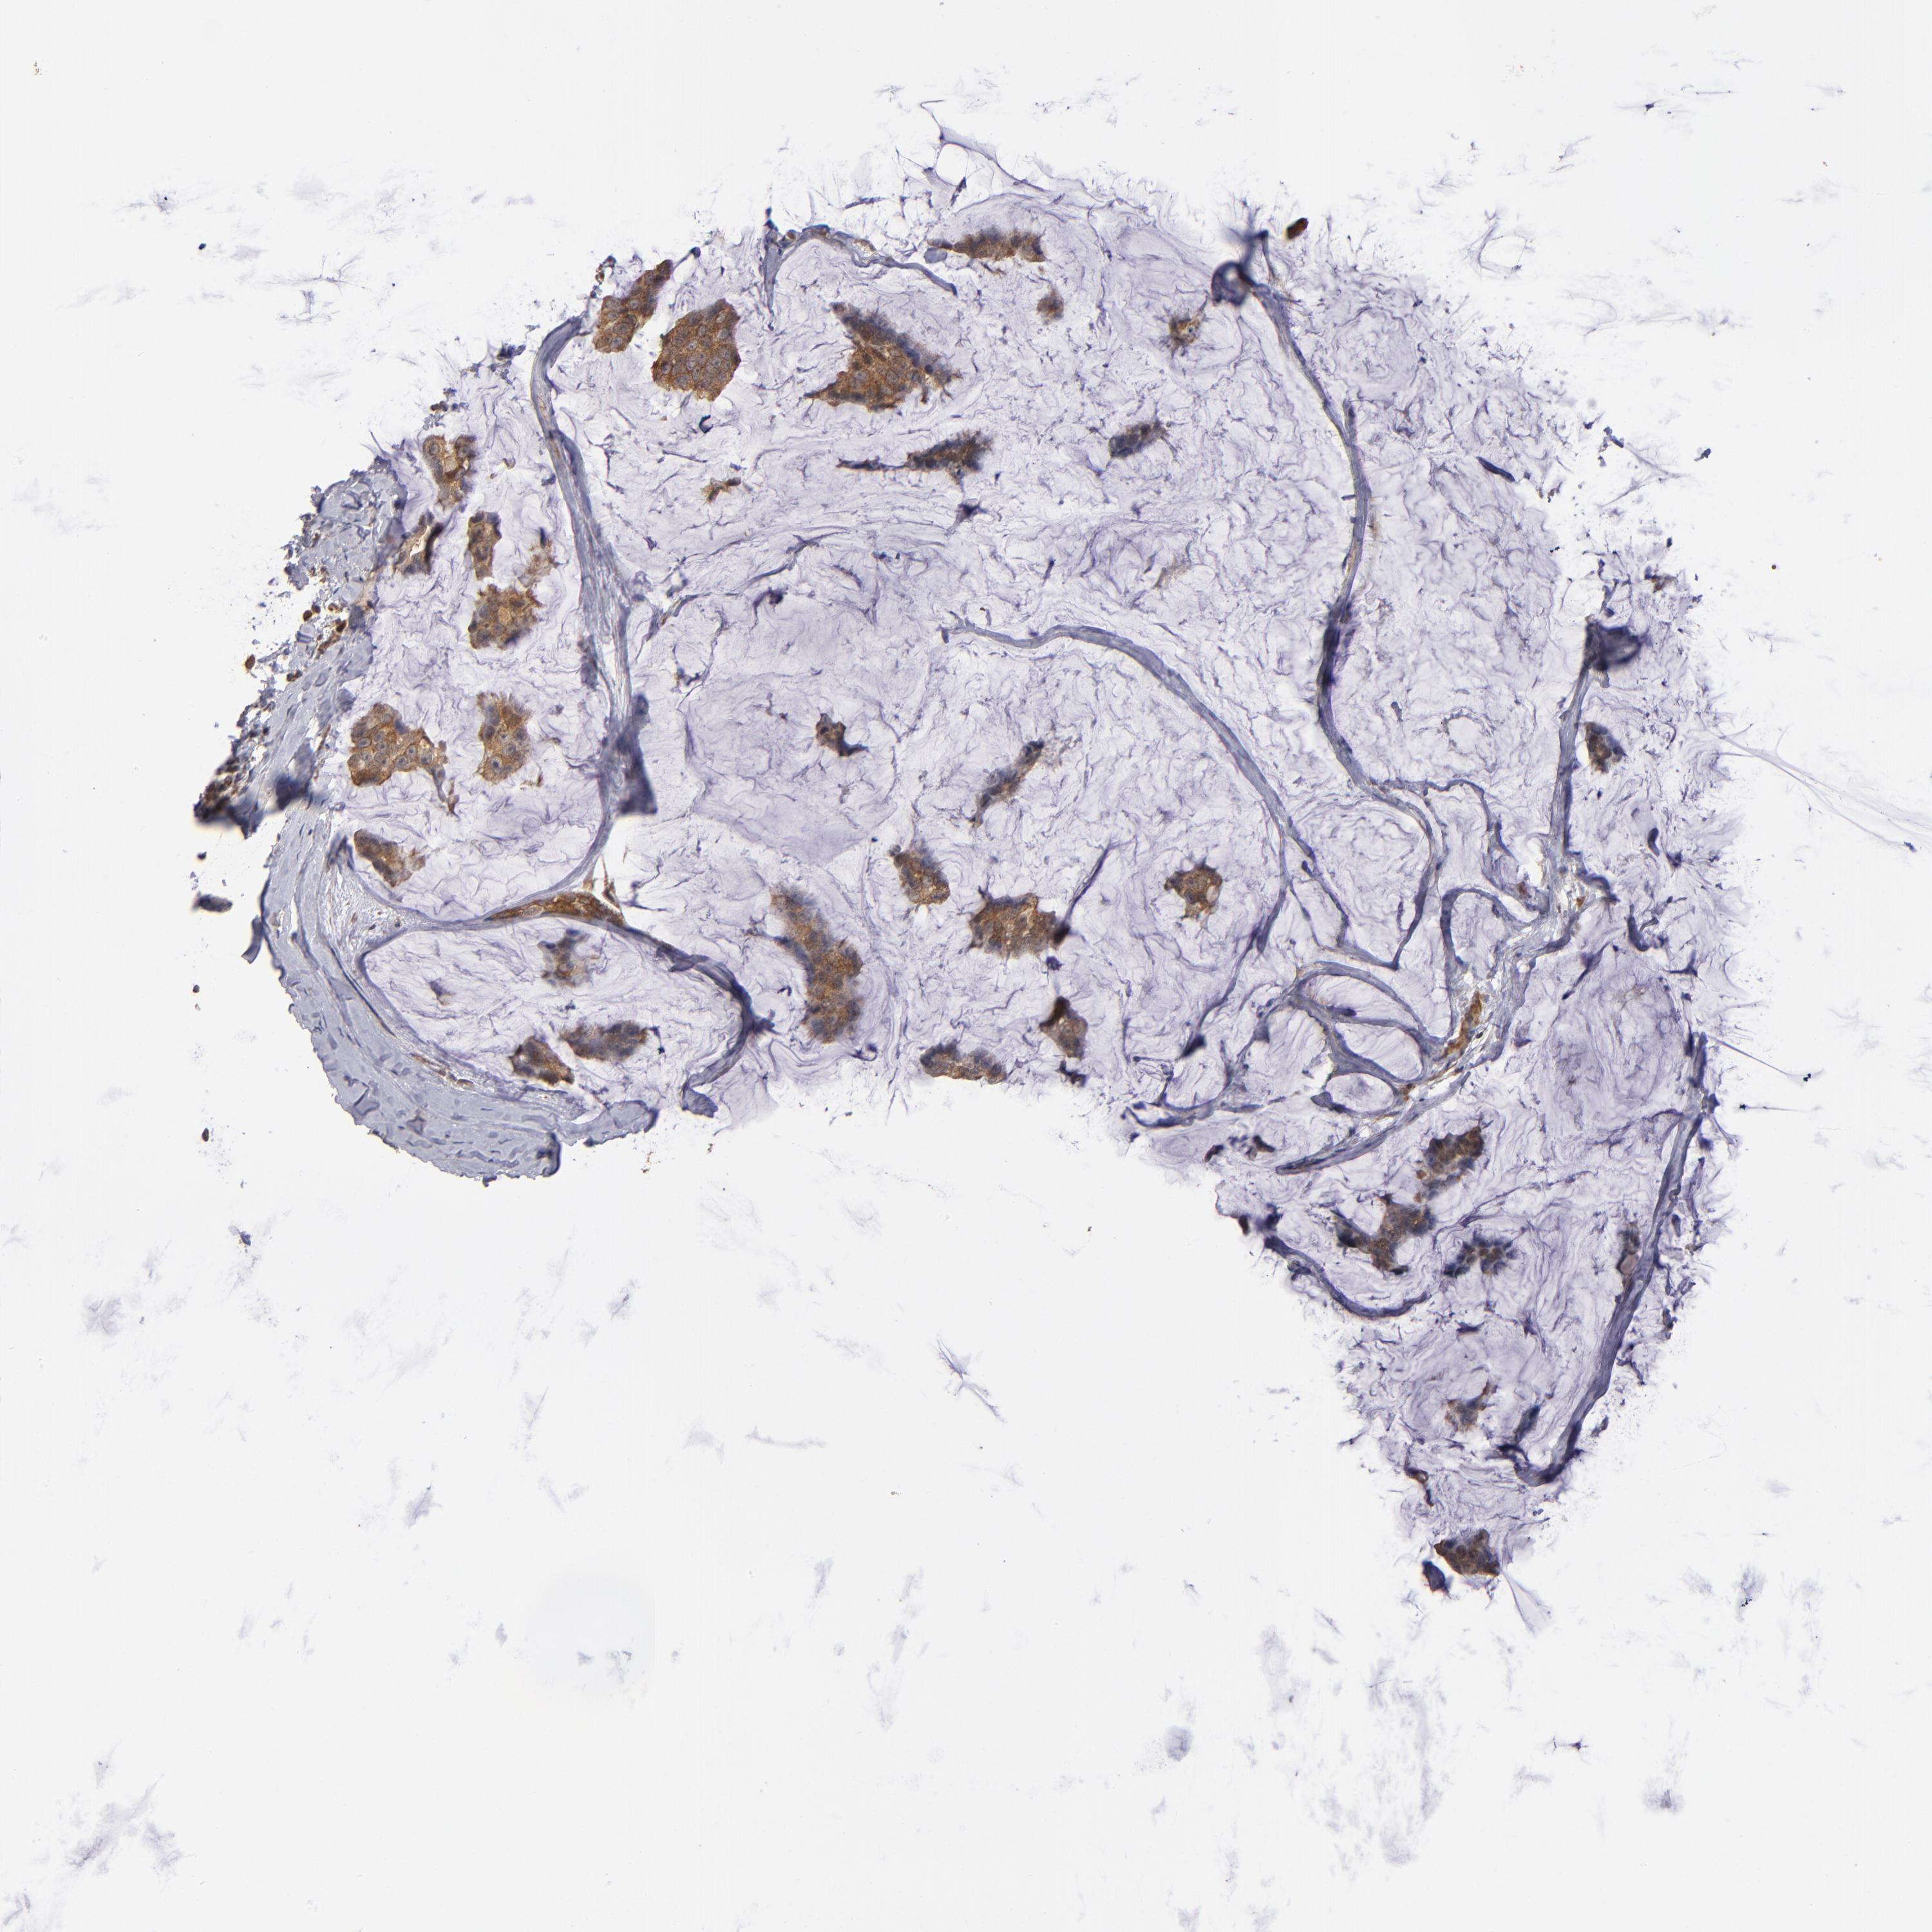

CANCER BREAST CANCER Show tissue menu

BRCA TCGA BRCA VALIDATION PROTEIN EXPRESSION

ANTIBODIES

AND

VALIDATION